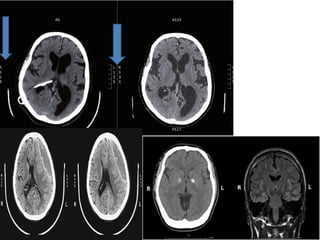

PRATIQUEZ VOUS AVEC CES CAS

CLINIQUES (3)

Hémiplégie droite de survenue brutale chez un

homme de 71 ans

INTERPRÉTATION

A. Le scanner cérébral sans injection réalisés heures après le

début des troubles montre des signes précoces d'infarctus

cérébral dans le territoire sylvien gauche avec un

effacement du noyau lenticulaire G et une

dédifférenciation substance grise-substance blanche dans

la région fronto-pariétale G.

B. L'angioscanner du polygone de Willis montre le thrombus

avec une interruption du flux dans l'artère sylvienne G.

C. Le scanner cérébral à 3 semaines montre une

hypodensité étendue témoignant d'un infarctus sylvien G

total.

Diagnostic : Infarctus sylvien gauche total

INTERPRÉTATION TYPIQUE DE

L’EXEMPLE PRÉCÉDENT 3 FIGURE A

Il s'agit d'un TDMcérébrale sans injection de PDC avec une coupe

axiale, fenetre parenchymateuse ,ETAGE SUS-TENTORIELE,

objectivant une:

 DES signes précoces d'infarctus cérébral dans le territoire sylvien

gauche avec un effacement du noyau lenticulaire G et une

dédifférenciation substance grise-substance blanche dans la région

fronto-pariétale G. Effacement des sillons corticaux du côté de la

lésion

 ABSCENCE D’EFFET DE MASSE

 abscence de déviation de la ligne médiane

 Absence d'hémorragie méningé

 structure de la ligne médiane en place

 abscence de lésion osseuses